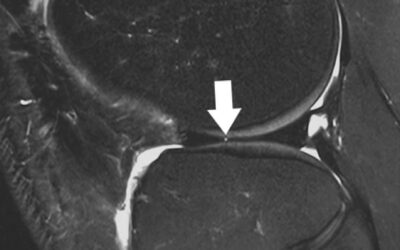

AAOS Updates Clinical Practice Guideline for Management of Acute Isolated Meniscal Pathology

In releasing its new clinical practice guideline (CPG) focused on acute...